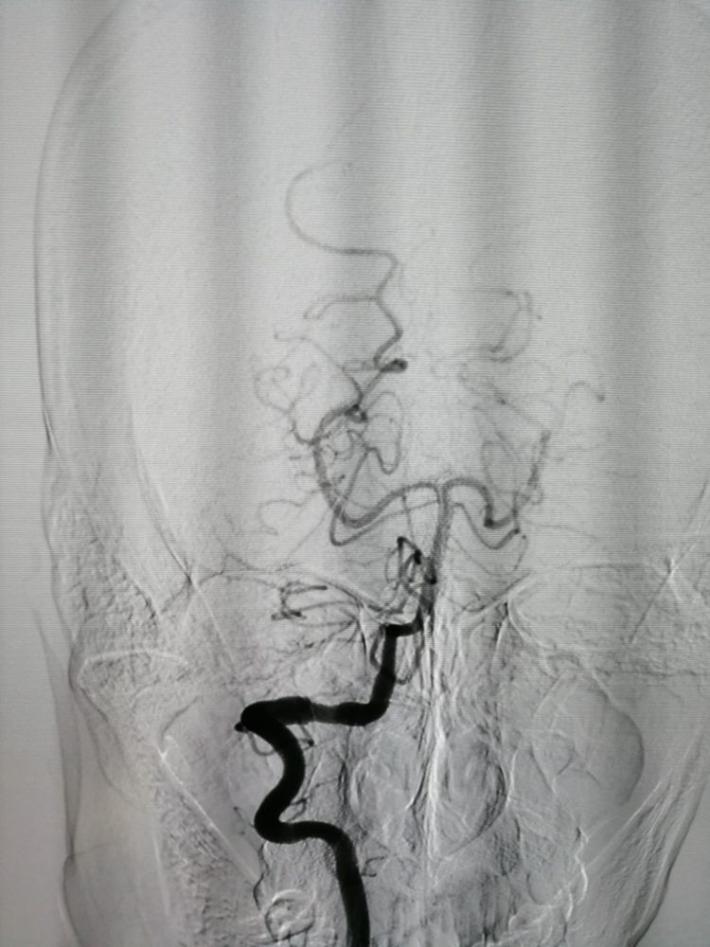

拟行介入栓塞术,术前(发病一周)再造影,前交通动脉瘤“消失了”!

以原造影3D为依据,选择一角度再造影,见动脉瘤“若隐若现”,但路图上动脉瘤仍不显影,仔细观察血管,见同侧A1、回返动脉较前一日痉挛,分析系此因素加上动脉瘤小且窄颈的原因导致造影剂进入动脉瘤内太少,以致动脉瘤显影不良。考虑瘤体很小,路图上又不显示,盲目栓塞风险很大,决定终止手术,改行开颅夹闭。